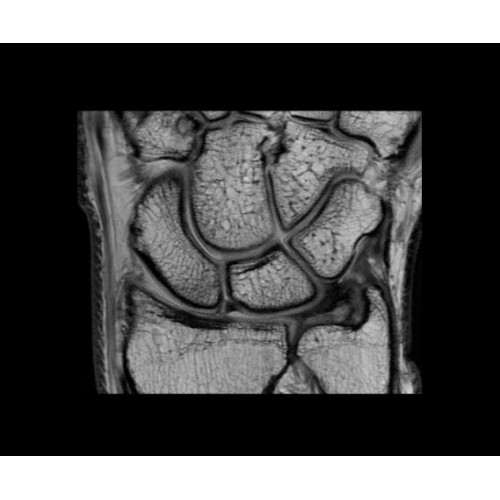

Поле обзора 50x50x50 см и апертура шириной 70 см позволят достоверно визуализировать сложные анатомические области для пациентов с крупным телосложением, например, плечи и бедра. Феноменальная однородность системы SIGNA Architect обеспечивает наиболее широкое поле обзора с улучшенными характеристиками градиентов. Ничто не останется незамеченным.

• OrthoWorks — программное решение для визуализации структур опорно-двигательного аппарата с прекрасным контрастированием тканей.

• Digital Surround Technology (DST)— это новая технология объемной оцифровки данных, которая объединяет сигналы от каждого элемента катушки. Прекрасное соотношение сигнал/шум и чувствительность поверхностных катушек в сочетании с превосходной однородностью и высокой проникающей способностью встроенной радиочастотной катушки — все это позволяет создавать качественные изображения не только позвоночника, но и всего тела.